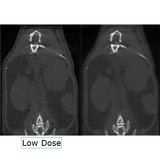

The X-CUBE is our high throughput CT “work horse”. It allows for fast whole body mouse and rat CT imaging at extremely low dose and excellent soft tissue contrast.

Light weighted thanks to a self-shielded imaging unit it is a truly mobile in vivo scanner. Advanced workflows such as gated and dynamic contrast enhanced imaging can be achieved in a functional and integrated set up. Our iterative reconstruction techniques are available in standard as well as expert user mode. Intuitive and wireless acquisition software combined with our multimodal small animal bed allow for easy and modular multimodal imaging along with the γ-CUBE (SPECT) and β-CUBE (PET).